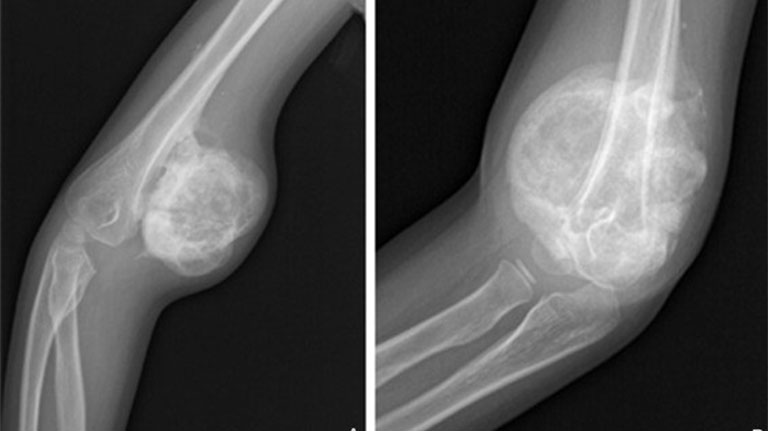

- Chụp x-quang

Nếu khối u lành tính, bác sĩ có thể khuyên bạn chỉ cần theo dõi chặt chẽ để xem nó có thay đổi hay không. Trong thời gian này, bạn có thể cần chụp X-quang theo dõi định kỳ hoặc các xét nghiệm khác.